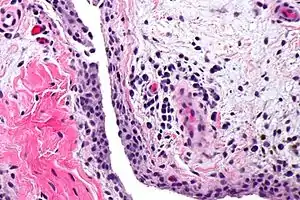

| Chronic synovitis | |